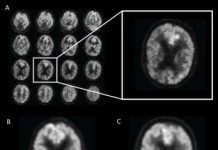

Tech: Artificial intelligence predicts Alzheimer’s years before diagnosis — (Report)

Artificial intelligence (AI) technology improves the ability of brain imaging to predict Alzheimer's disease, according to a study published in the journal Radiology.